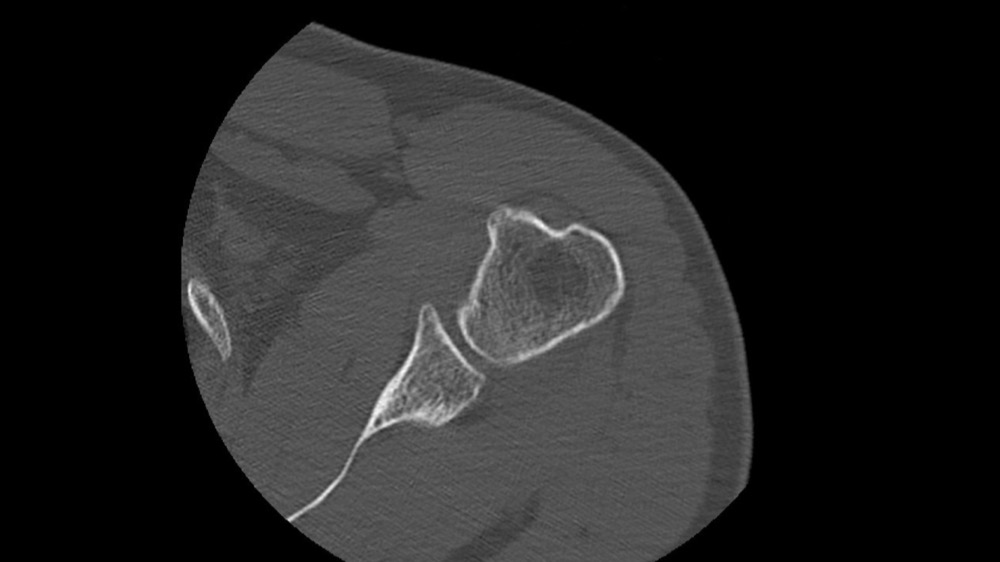

Gortais / Biyoukar / Miquel / Parlier-Cau 19/01/2022